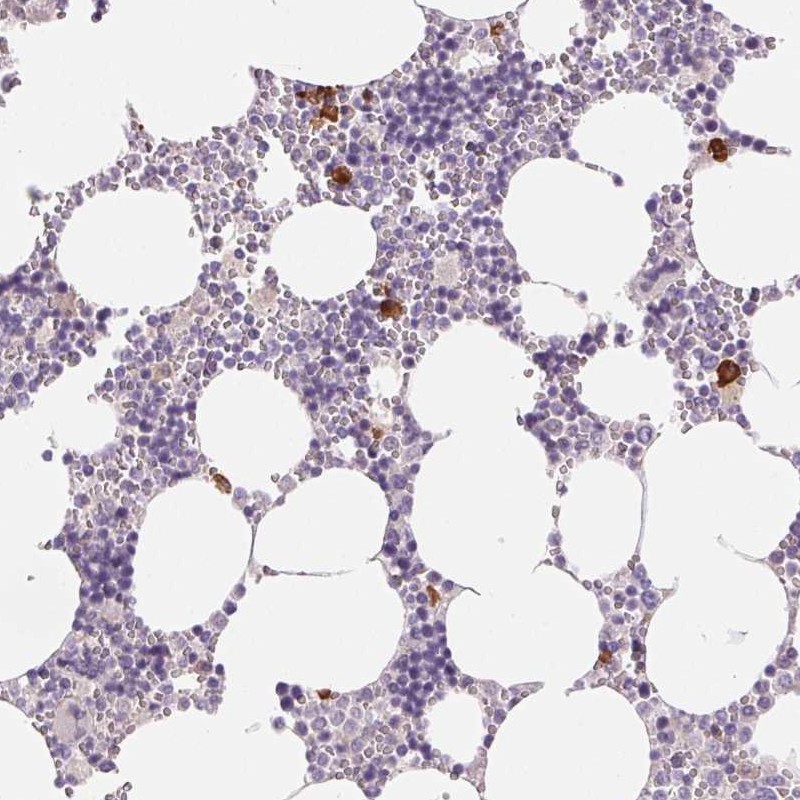

Immunohistochemical staining of human bone marrow shows strong cytoplasmic positivity in a subset of hematopoietic cells.